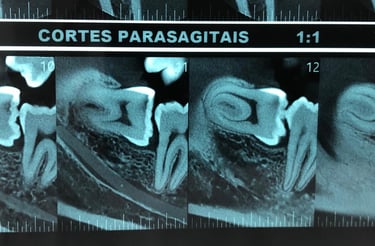

O planejamento da cirurgia dos dentes do siso normalmente é realizado por meio de tomografias computadorizadas. Elas permitem visualizar com precisão a localização do canal mandibular (seta), cuja lesão durante a cirurgia pode causar complicações neurossensoriais e hemorragias, reforçando a importância de um bom planejamento cirúrgico.